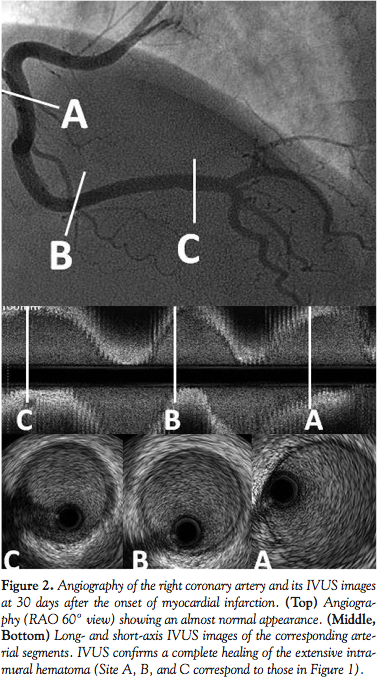

identified no visualization of an intimal tear which suggested any entry point of coronary artery dissection.1 After intracoronary injection of isosorbide dinitrate, the severe stenosis regressed to moderate spontaneously. As no flow limit and no observation indicating ongoing ischemia were recognized, neither balloon angioplasty nor stenting were performed. His 9-day hospital stay was uneventful and without recurrent episodes of angina. We performed a follow-up coronary angiography at 30 days after the index procedure without any abnormal finding of the right coronary artery. IVUS delineated a complete restoration of the intramural hematoma (Figure 2). No inducible coronary spasm was observed by means of an intracoronary ergonovine maleate.